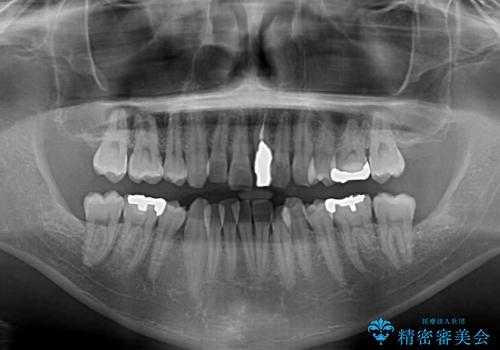

- 下顎の八重歯を気にして来院された患者様です。

左下以外、3本の第一小臼歯が既に抜去されており、左下は八重歯になっている状態でした。

左下の八重歯は手前に傾斜していたため、インビザラインによる抜歯矯正が可能と判断し、後方にある第一小臼歯を抜歯してインビザラインにて矯正治療を行うこととしました。